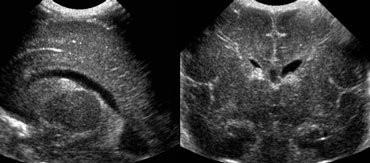

Classic PVL 22-32 weeks

Classic PVL

“Flare”

Normal day 1-7

Grade I

Persists after day 7

Acute to Chronic PVL on MRI (often at Term)

White Matter Injury of Prematurity

 Acute 2-4 days

 WM T2 Hyperintensity

 Foci of focal T1 shortening, not hemorrhage

 Late acute/subacute phase

 T1 shortening:

▪ Hemorrhage

▪ Inflammation (microglial inflammatory activation)

▪ Reperfusion in setting of weakened capillaries & increased venous pressure

White Matter Injury of Prematurity = PVL

Term Equivalent MRI – imaging often not specific

Flare/PVL at 28 weeks

Term Equivalent Late changes

PVHI at 32 weeks

Term Equivalent